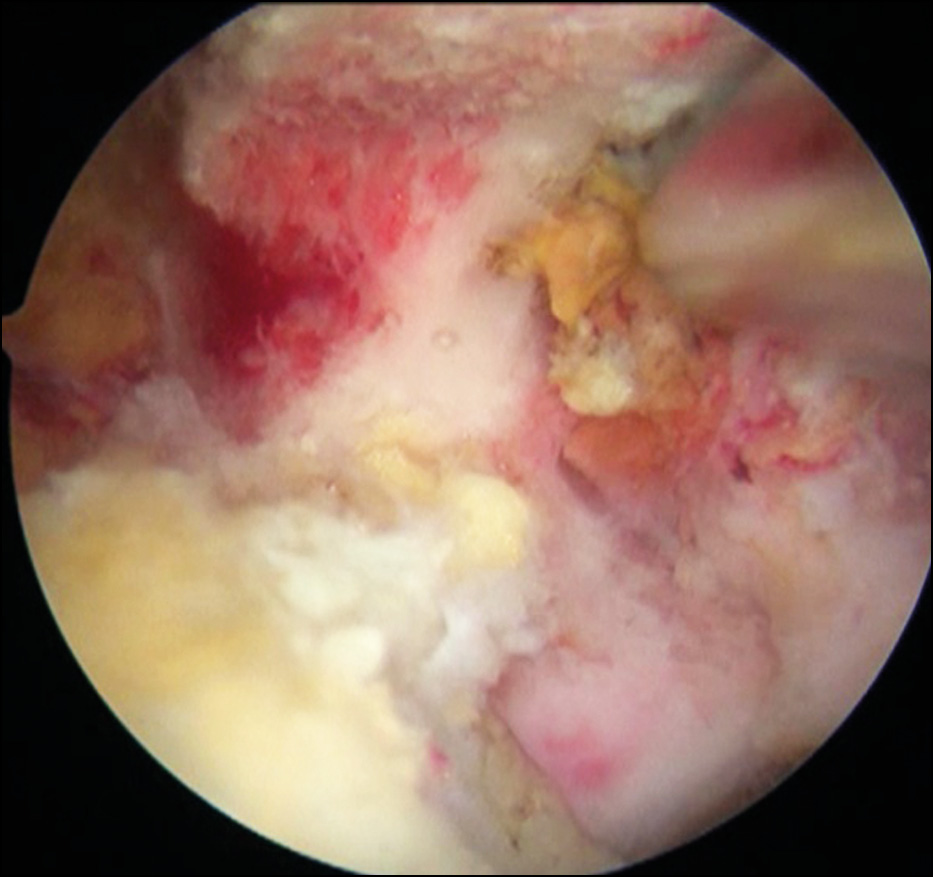

Then, the joint capsule was mobilized, the rotator interval was widened using a shaver and a coblator, degenerative areas of the articular lip and the acromioclavicular ligament were resected in the anterior–inferior section through the 5 o’clock position (Fig. 5).

Fig. 5. Treatment of a safe rotatory interval with a shaver and coblator: a — access implementation; b — mobilization of the capsule and expansion of the rotator interval.